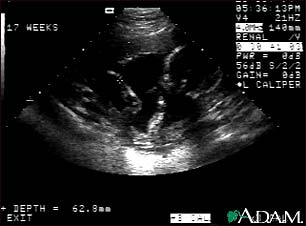

Ultrasound, normal fetus - arm and legs

This is a normal fetal ultrasound performed at 17 weeks gestation. This is the type of image pregnant mothers may see on the ultrasound screen, or that the technician may print. It shows the head on the right, and the cross hair pointing to the left ankle. The left leg and arm are visible in the center of the screen.